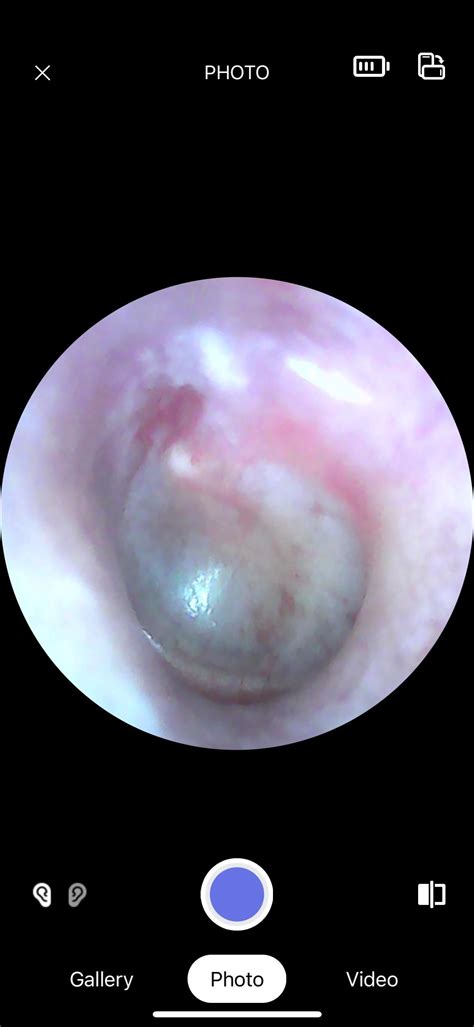

Healthy Ear Drum

• Otoscope: A device with a light and magnifying lens used to examine the ear canal and ear drum.

• picture of a healthy eardrum

• healthy ear drum otoscope

• normal ear drum look like